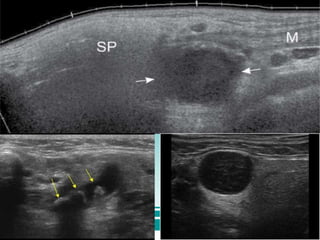

₴.Ultrasound

Non invasive, less costly and maybe able to

visualize radiolucent calculi

Limitation

o May not be able for correct assessment of

the number of calculi

o Calculi less than 2mm may not produce an

acoustic shadow

₴.Ultrasound Non invasive, lesscostly and maybe able to visualize radiolucent calculi Limitation o May not be able for correct assessment of the number of calculi o Calculi less than 2mm may not produce an acoustic shadow